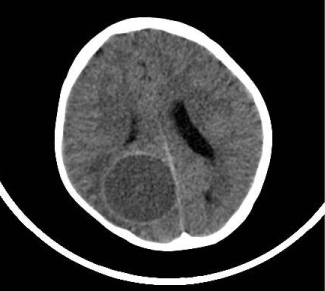

An 8-year-old boy who was living in countryside, was brought to ER because of vomiting due to head trauma. His neurological examination was normal. CT scan revealed a cystic lesion in right parieto-occipital region with approx. 5 cm diameter (Figure 1). By cranial MRI large cystic lesion with periferal enhancement was detected (Figure 2). Indirect hemagglutination was negative. Before surgery, 15 mg/kg/d albendazole treatment was administrated. Further examinations revealed no other involvement in body. Right parieto‑occipital craniotomy performed and lesion was totally excised. Post-operative recovery was uneventful. In pathological examination, fibrous wall was excised and smooth semi-transparent hydatid cyst was seen (Figure 3). Albendazole treatment was continued. Cranial MRI at the post-op 2nd month revealed no pathological findings (Figure 4).